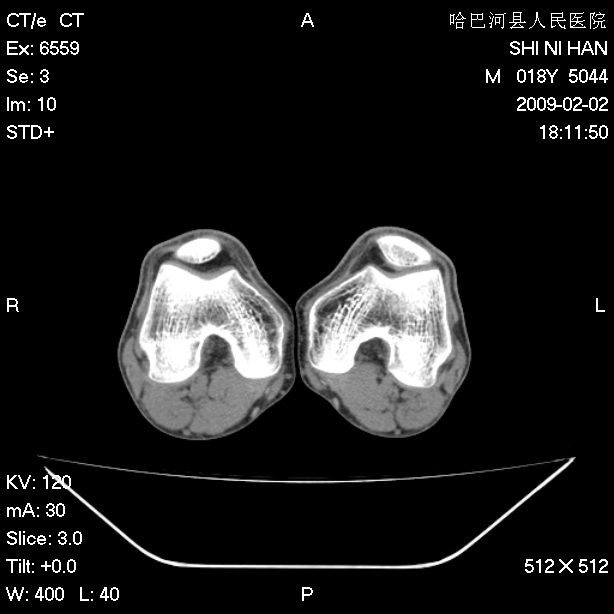

标题: CT17889:外伤后右膝关节反复疼痛3年余 [打印本页]

标题: CT17889:外伤后右膝关节反复疼痛3年余

ct未见明显异常。关节腔未见明显积液,半月板未见明显撕裂。但最好还是mri看看韧带及半月板情况。